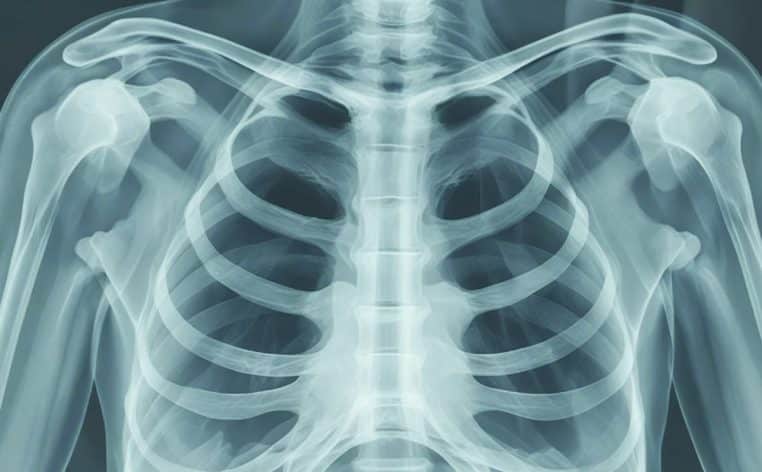

Ce cas médical est bien entendu très rare, et a soulevé de nombreuses interrogations auprès des spécialistes. L’imagerie médicale a démontré que le couteau a bien failli toucher les organes vitaux de la victime. L’arme a été insérée par le dos de l’homme, près de l’omoplate droite, avant de se glisser entre sa cinquième et sa sixième côté. La pointe du couteau, elle, s’est retrouvée entre la troisième et la quatrième côté, très proche du cœur et des poumons. Lors des faits, l’homme avait eu des fractures osseuses qui s’étaient guéries avec le temps.